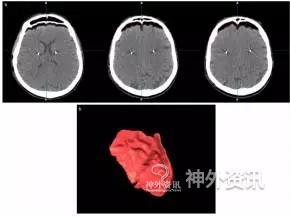

该研究共纳入85例患者,涉及158个大脑半球,植入165枚电极。根据术中骨孔大小将患者分为小骨孔组(直径4mm),涉及71个大脑半球;大骨孔组(直径14mm),涉及87个大脑半球(表1)。通过术后即刻复查CT平扫图像计算颅内积气体积(图1),对比两组患者“骨孔侧大脑半球前方的颅内积气量”是否具有统计学差异。

图1. 颅内积气体积计算示例。上图:CT平扫轴位片示大脑前方与颅骨间存在积气;下图:颅内积气的三维重建。